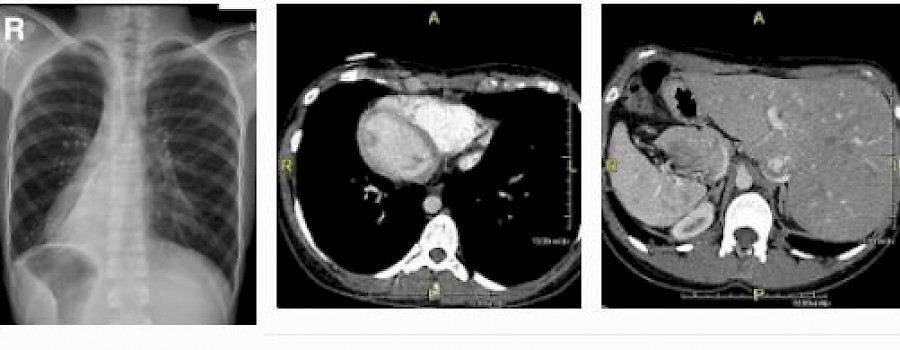

Fremdkörper aus Baumwolle

Gossypibom

Als Gossypibom wird in medizinischen Fachkreisen ein zurückgelassener Frempkörper aus Baumwolle nach chirurgischen Eingriffen bezeichnet. Der Ausdruck Gossypibom setzt sich zusammen aus „gossypium“ (lateinisch: Baumwolle) und „boma“ (Swahili: Versteck).